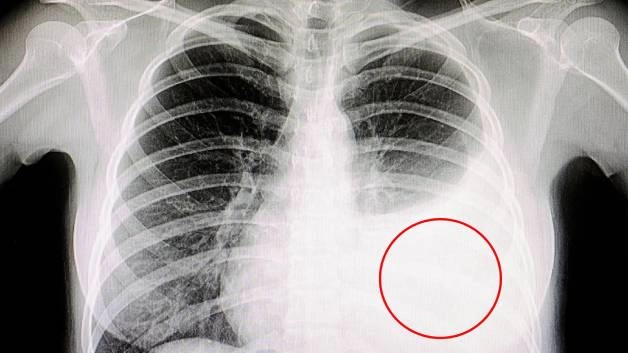

Hình ảnh ung thư biểu mô màng phổi trên phim chụp

– Chụp X-quang ngực: Đánh giá những thay đổi bất thường trong màng phổi như dày màng phổi, tràn dịch màng phổi,…